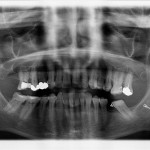

Perchè realizzare l’ortopantomografia direttamente nel proprio studio odontoiatrico

L'odontoiatra è probabilmente la figura medica che, fatta eccezione ovviamente per lo specialista in radiologia e diagnostica per immagini, fa più frequentemente uso di...